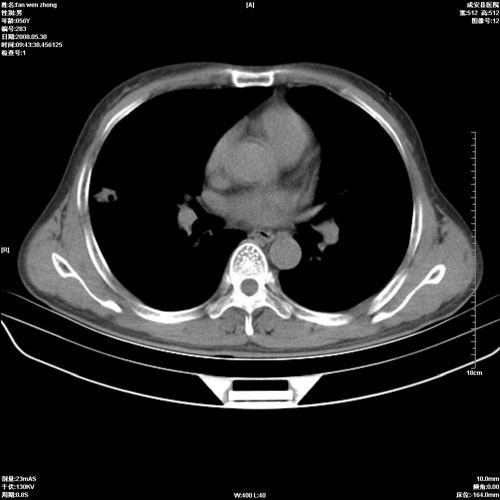

病人 男 56岁 一周前高热,体温达39-40度,经抗炎治疗后,体温渐降,达37,5-38度,轻微咳嗽,胸部不适 查白细胞为1.3万 行ct检查,请分析。

双肺内可见多发结节状病灶,并见小空洞,病人高热,白血球增高,应该是典型的迁徙性肺脓肿(多为金黄色葡萄球菌感染)。查一下口腔等其它部位有无感染灶。

双肺内可见多发结节状病灶,并见小空洞,病人高热,白血球增高,应该是典型的迁徙性肺脓肿(多为金黄色葡萄球菌感染)。建议治疗后复查.